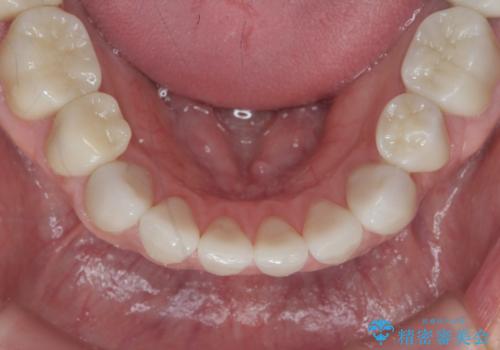

神経を温存したまま仮歯に置き換え、噛み合わせの安定を確認したのちに すり減りに強いジルコニアクラウンで最終的な仕上げを行います。

- 145.2万円(仮歯・ジルコニアクラウン×12歯)費用は治療当時の料金となります

歯の形態・色調を大きく変更する場合ジルコニアクラウンによる治療が耐摩耗性・審美性の観点から推奨されます。